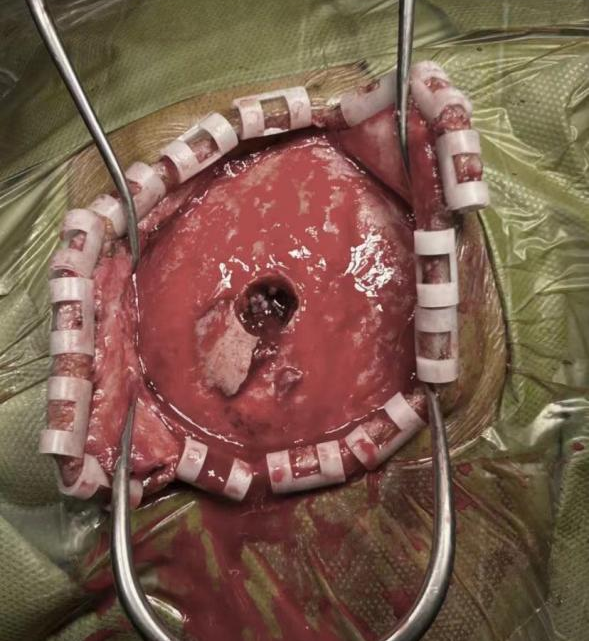

神经外科黄煜伦主任、肖宗宇副主任对病情进行评估后,决定立即进行急诊开颅手术。术中可见脑组织已从伤口疝出,一枚较大骨片刺入矢状窦,矢状窦出血严重。遂予以自身骨膜修补重建矢状窦,清除挫伤脑组织。整个手术过程中,医护人员紧密配合,沉着冷静,团结一心,认真负责,手术进展顺利。

术中暴露钢筋颅骨穿刺口及刺入矢状窦骨片